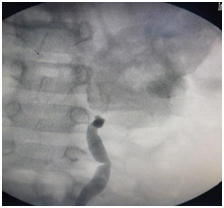

| Preoperative intravenous pyelogram | Postoperative intravenous pyelogram | |